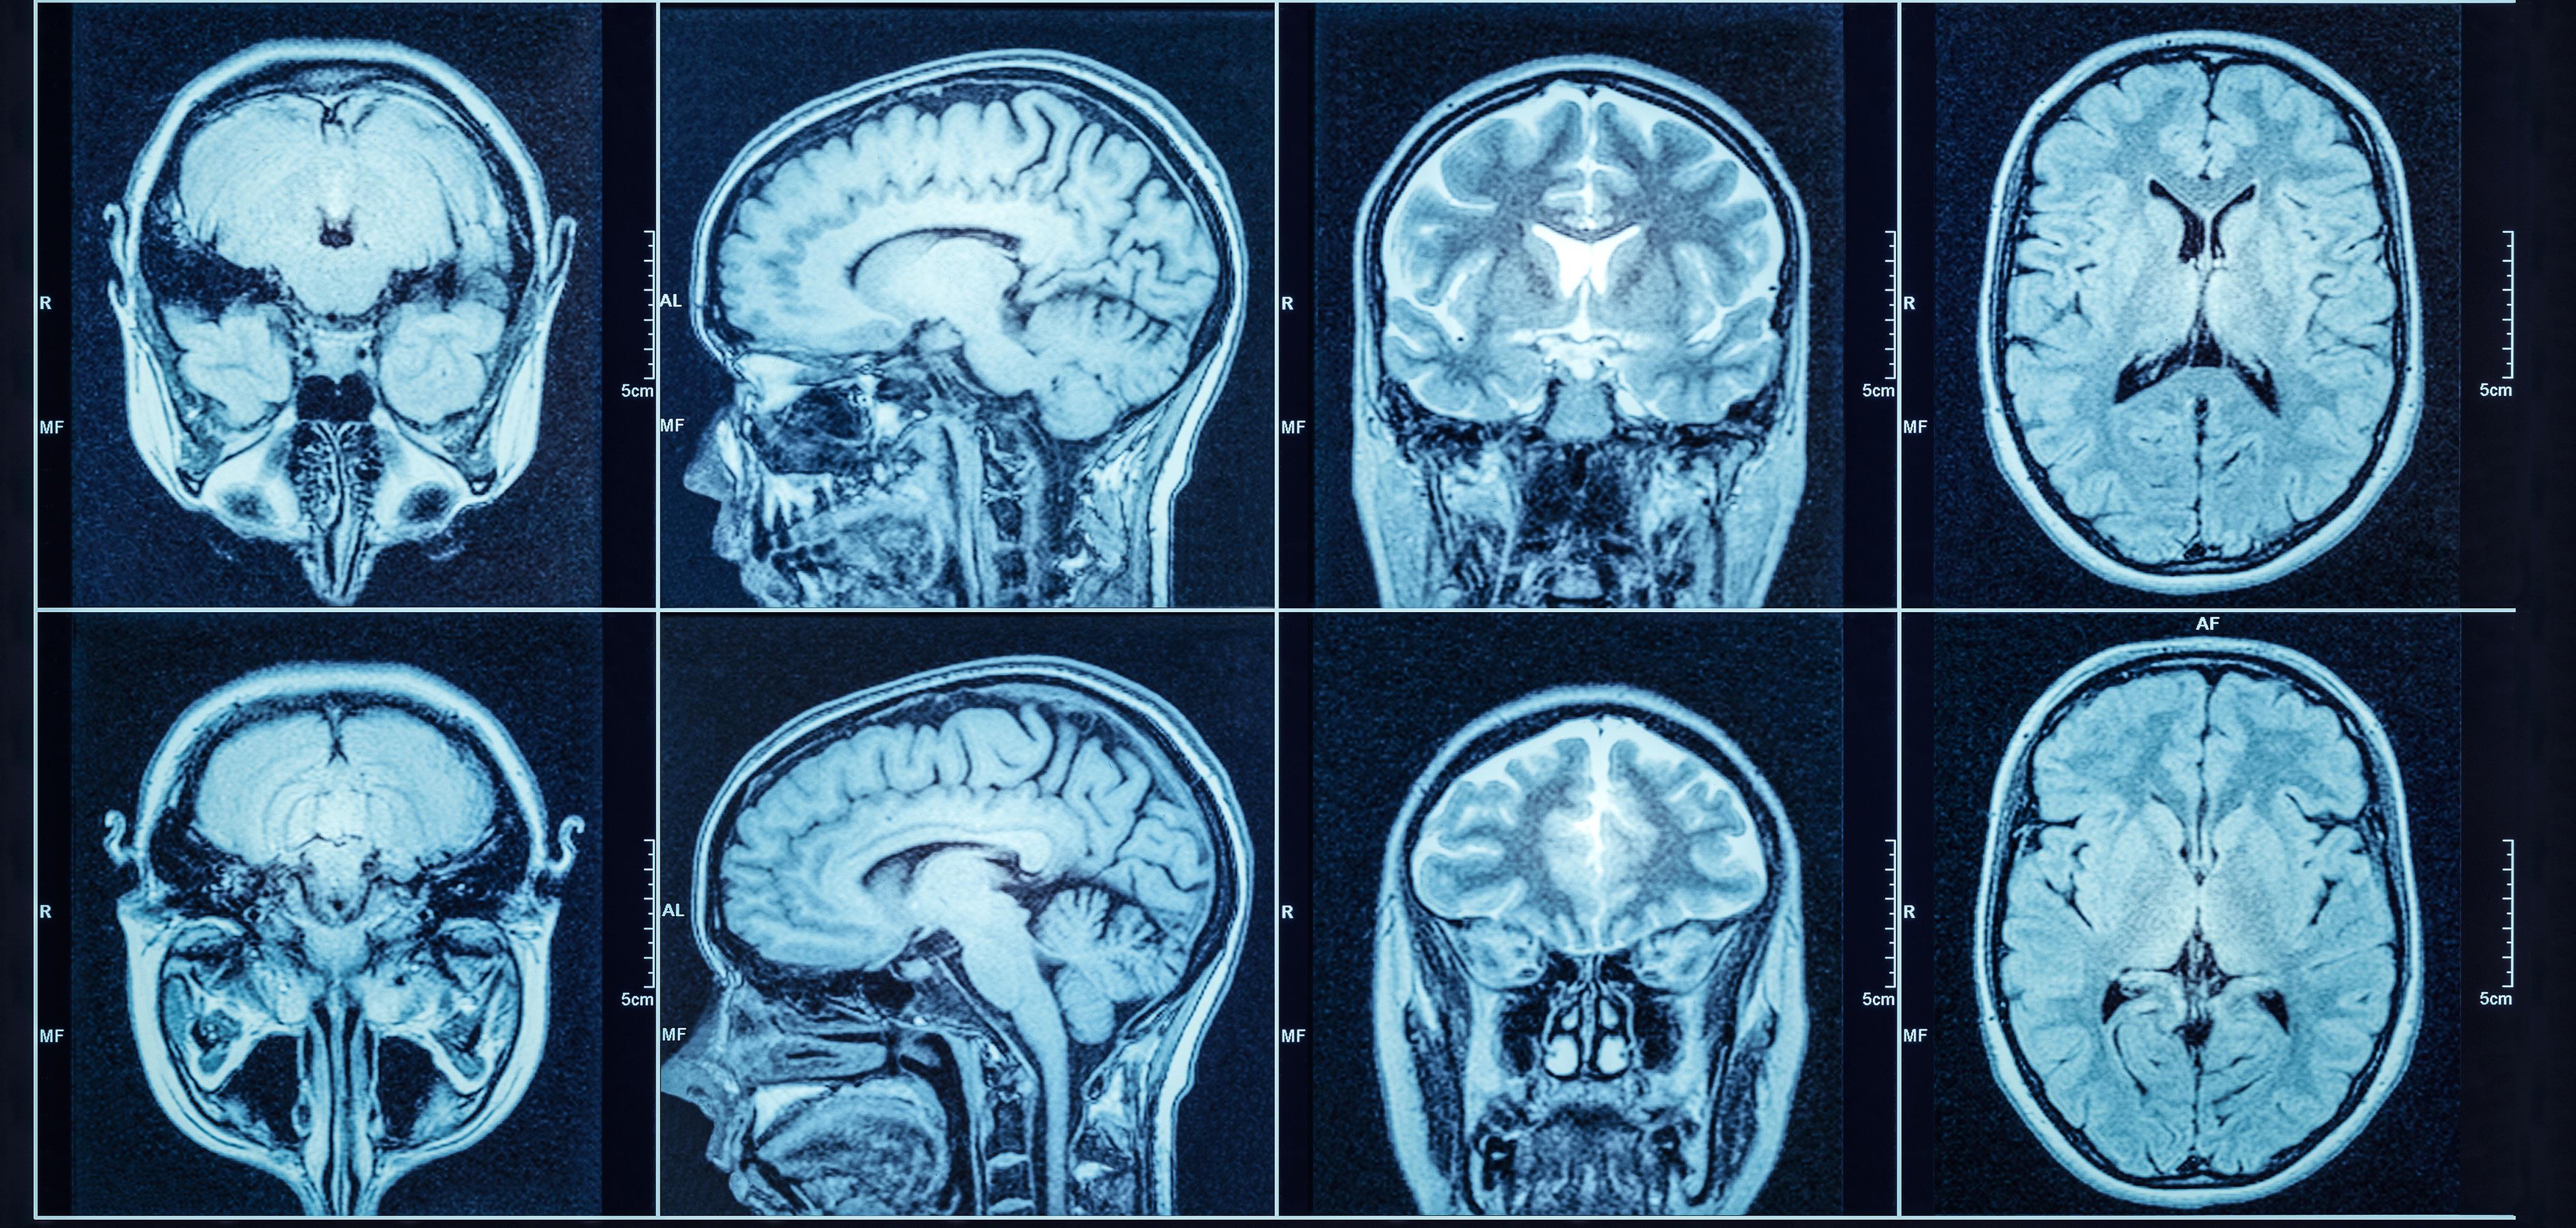

WHOLE BODY MRI SCREENING

Whole-body MRI is very effective in detecting cancer at an early stage. Large studies have shown that 1-2% of people over 40 have cancer on whole-body MRI screening.

Early diagnosis can make treatment more effective.

Over 2,000 images of your body.

• Head and neck, including the brain and skull.

Chest, including lungs.

Abdomen and pelvis: including the pancreas, liver, gallbladder, kidneys, adrenal glands, bladder.

Reports by expert UK radiologist.

No exposure to X-rays or radiation.

Can detect cancer before symptoms appear.

Comfortable scanning environment.

Doctor's guidance at all steps for positive results.

All scans are at imaging centres in Central London. Chosen for their expert radiologists.